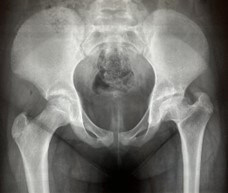

Results: We studied 20 patients with Meyer's dysplasia, representing 1.4% of LCPD cases in children. The majority were boys (85%) with symptom onset at 38 months. Claudication (25%) and mild pain (40%) were the main complaints. Radiographic findings showed a smaller, granular, or asymmetric nucleus. The average follow-up was 6.4 years, with interventional treatment in 5 cases. Most showed complete reossification and centralization of the femoral head.

Abstract Image